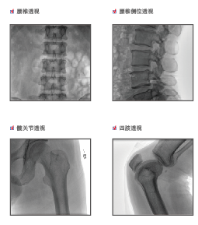

普愛醫(yī)療是專業(yè)從事平板小C生產、研發(fā)、售后為一體的廠家,目前我們應用在國內很多醫(yī)院的一款PLX118F平板C形臂,它是一臺集光、機、圖像處理技術為一體的帶數(shù)字減影血管造影功能(DSA)的可移動式X光機,該設備占地面積小、圖像清晰、定位精準、輻射劑量小,是疼痛科醫(yī)生的可靠眼睛,對于疼痛介入手術的精準化治療、滿足患者對慢性疼痛治療需求提供了有利條件。